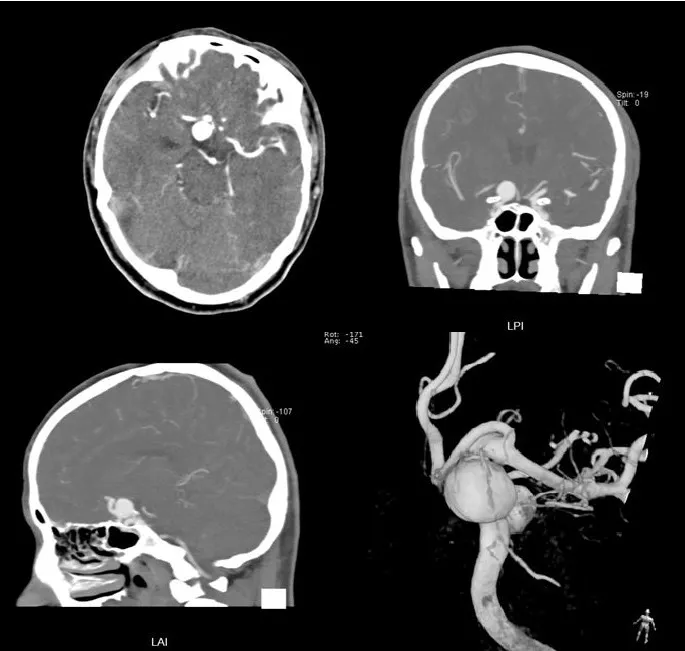

入院后完善CTA,DSA等检查提示颅内多发动脉瘤:

其中右侧颈内动脉眼段动脉瘤(约13.8*14mm大小,瘤颈8.04mm)。和家属沟通病情,告知介入和开颅手术两种治疗方式的风险利弊后,患者家属选择开颅右侧眼动脉段动脉瘤夹闭手术治疗。

进一步行DSA+CT融合,模拟手术入路视角。